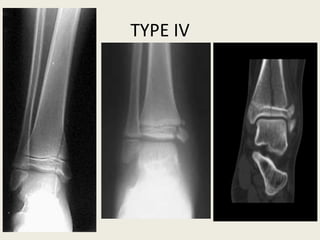

• Accounts for 10% of all physeal injuries.

• Vertical fracture through all three components, metaphysis, physis and

epiphysis.

• These fractures are liable to displacement and a consequent misfit between

the separated parts of the physis, resulting in asymmetrical growth

• In type IV separations, the fracture line is vertical. It extends through four

distinct tissues/areas: metaphyseal bone, physeal cartilage, epiphyseal

bone or cartilage and articular cartilage.

• The most common example of a type IV physeal injury is separation of the

lateral condyle of the distal humerus.

• The four injured tissues must be accurately reduced and lined up with each

other, to minimise the risk of a physeal bar and articular incongruity.

• Most displaced type IV injuries require ORIF and long-term follow-up to

detect growth disturbance.

TypeIV

TYPE IV